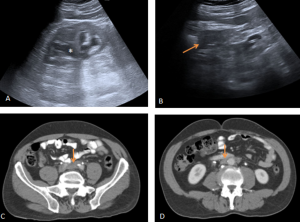

ULTRASONOGRAPHY (US)

Useful as screening, but with low sensitivity.

RPF is visualized as a hypo or anechoic, irregular demarcated retroperitoneal mass, anterior to the lower lumbar spine or the promontory of the sacrum.

If ureteral entrapment is present, ureterohydronephrosis may occur in varying degrees.

MULTIDETECTOR COMPUTED TOMOGRAPHY (MDCT)

MDCT may fail to demonstrate abnormalities in approximately one third of surgically proven RPF cases.

RPF typically appears as a well-defined, irregular paraspinal soft-tissue mass, isodense to the psoas muscle and without lateral extension beyond it. Most often centred at L4–L5 near the aortic bifurcation, it may extend cranially towards the renal hila or, less commonly, caudally to involve pelvic structures. Baseline Hounsfield units (HU) values and the diameter of the retroperitoneal tissue can assist in assessing inflammatory activity. [1,3,5-8]